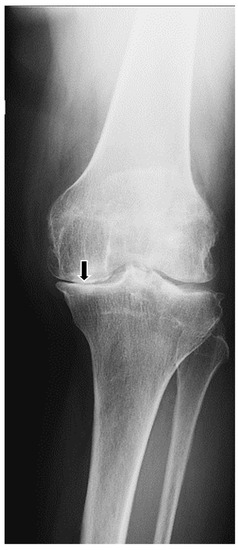

2. Case Report